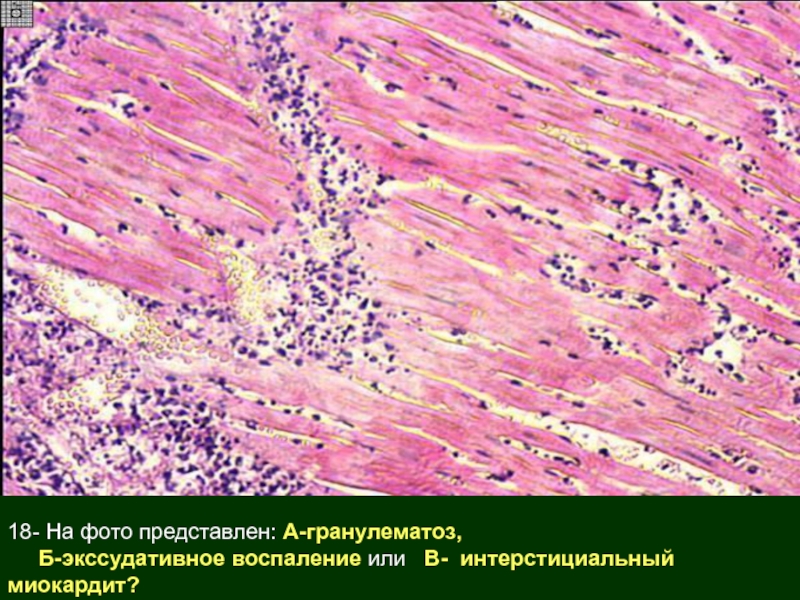

Межуточный миокардит: гистологические исследования

Раздел: Идеи и советы